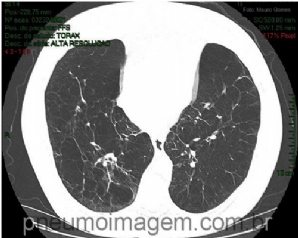

CASO CLÍNICO #3

Homem, 28 anos, apresenta-se com dispneia desde a infância, mas que se acentuou no último ano. Apresenta crises de chiado com tosse e expectoração purulenta eventualmente. Ao exame, emagrecido, dispneico, com MV diminuído globalmente e sibilos expiratórios dif...